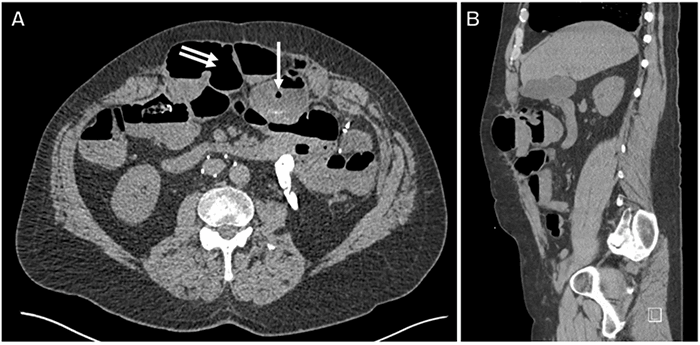

Several years later, the patient reported a three-day period characterized by diffuse abdominal pain, anorexia, nausea, vomiting, and no bowel movements. Upon arrival to the tertiary care center, the patient endorsed persistent abdominal pain. On physical exam, his abdomen was diffusely tender in all quadrants and high-pitched bowel sounds were present. A CT scan of the abdomen and pelvis with IV contrast demonstrated a focal segment of small bowel dilated to 4.4 cm, with a discrete transition point consistent with SBO (Figure 1). The CT also revealed an osseous projection arising anteriorly from the L3 vertebral body that joined with an osseous projection from the inferior left T12 rib and formed a pseudoarthrosis in the abdomen from a third projection—this third projection arose from the sternum/xiphoid process (Figure 2 and Figure 3) This finding was suggestive of trauma-related heterotopic ossification (HO)—indeed, this ossification wrapped around the small bowel (Figure 1A) and provided a clear potential for obstruction. A ventral hernia was also noted on imaging but did not appear to be the cause of the patient’s SBO. The patient was unaware of the ossification and denied chronic abdominal pain that might be related to the ossification.

Figure 1. Representative axial (A) and sagittal (B) CT images of abdomen, demonstrating dilation of small bowel to 4.4 cm within a ventral hernia sac (double white arrow) with a distinct transition point (single white arrow), consistent with low-grade small bowel obstruction.